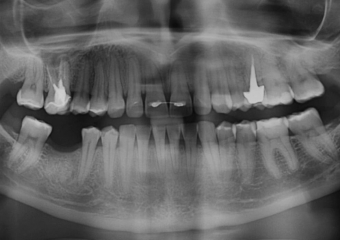

Raio X final após a prótese de porcelana instalada